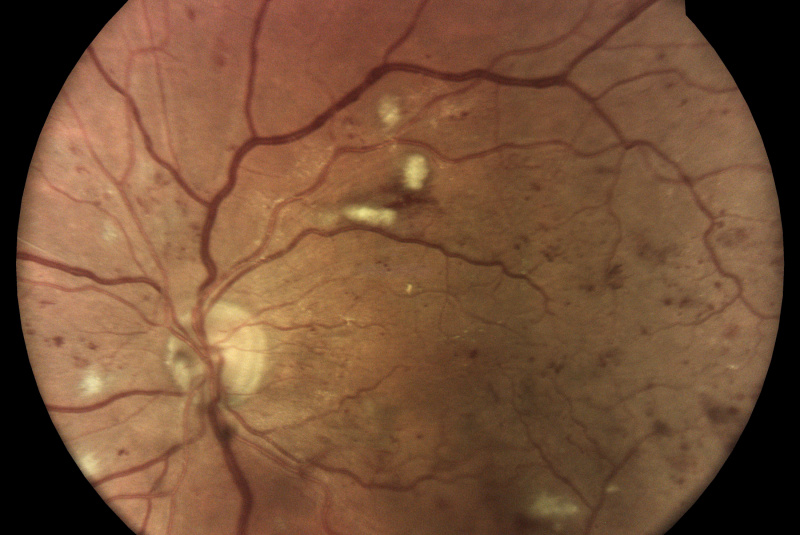

Z vysoko kvalitných fotografií očného pozadia zaobstaraných technológiou iCare DRSplus diagnostikuje diabetickú retinopatiu pomocou umelej inteligencie. Efektívny skríning vyhodnotený softwarom využívajúcim umelú inteligenciu iCare RETCAD®, je schválený pre klinické použitie a je klasifikovaný podľa certifikácie CE (0344) ako zdravotnícky prostiriedok triedy IIa, ktorý šetrí drahocenný čas ako lekára, tak aaj pacienta, umožňuje včasnú intervenciu a pomáha poskytovať včasnú starostlivosť. Analýza pomocou iCare RETCAD® nenahradzuje vyšetrenie zdravotného stavu očí.

AI (umelá inteligencia) okamžite rozpozná práznaky diabetickej retinopatie a klasifikuje výsledky podľa závažnosti na základe medzinárodných klasifikácií. Získate prehľad s hodnotením závažnosti záchytu, kde po analýze snímok zachytených kamerou iCare DRS Plus je automaticky generovaný report o pacientovi so stupnicou závažnosti pre diabetickú retinopatiu na základe medzinárodných štandardov (ICDR, AREDS).

Fundus kamera iCare DRSplus urobí celkovo 4 vysoko kvalitné True Color snímky (dve z pravého a dve z ľavého oka), ktoré sa automaticky ukladajú na cloud a posielajú sa na spracovanie AI - umelej inteligencii. Report je dostupný ihneď a ten je možné prekonzultovať s pacientom počas tej istej návštevy u lekára.